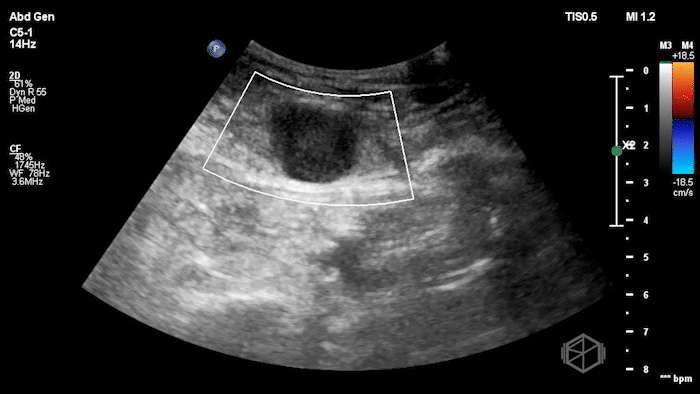

Given the patient’s focal abdominal wall tenderness, a POCUS exam of the left lower quadrant at the point of maximal pain was performed.

She obtained the following images:

The POCUS shows an hypoechoic circular mass within the rectus muscle. There is no active color doppler flow suggesting likely no active bleeding.

Diagnosis: Rectus sheath hematoma (RSH)